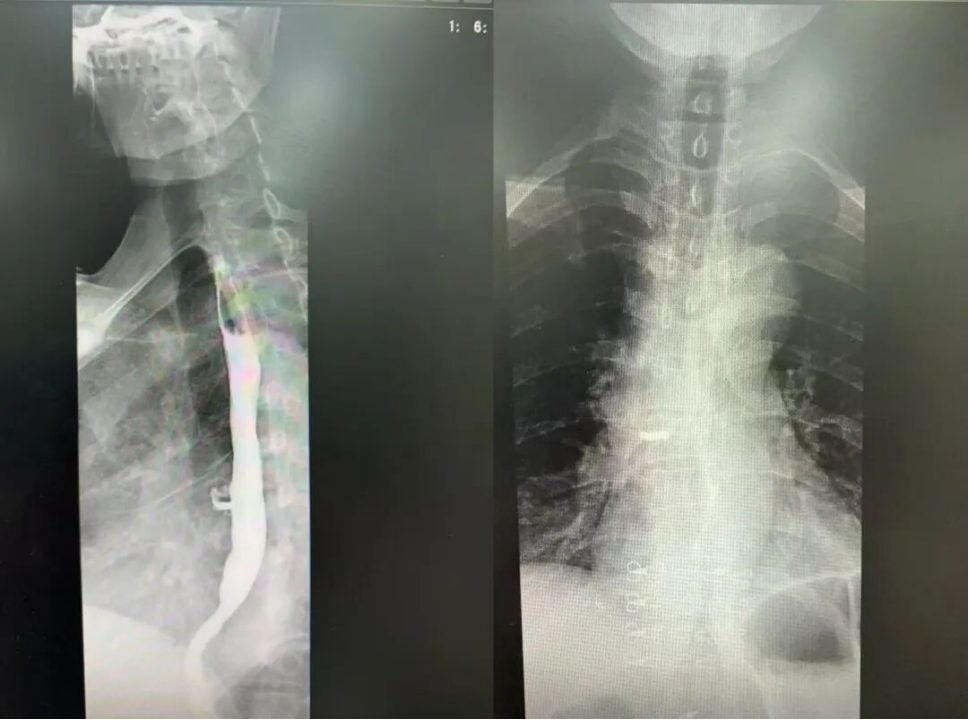

*患者术前食道造影

在多学科的通力配合下,这场近3小时的高难度微创手术顺利完成,患者术中出血少、生命体征全程平稳,术后平稳转入恢复室。随后,在胸部外科医护团队的悉心照顾下,马阿姨恢复良好,能经口进食,目前已顺利出院。